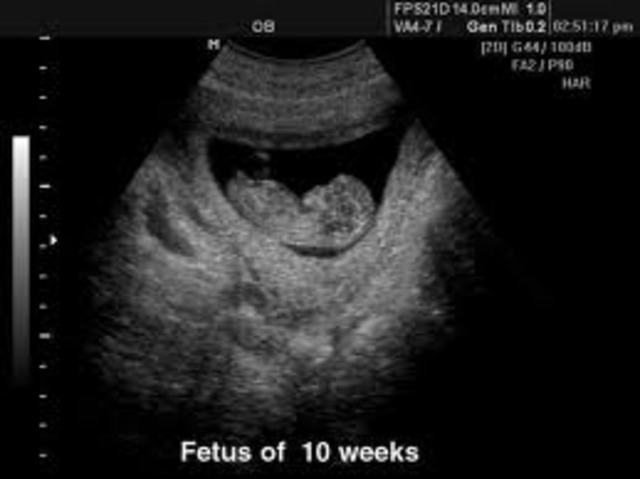

• 14 Weeks

14 Weeks

Your baby's kidneys are producing urine, and he releases it into the amniotic fluid. He can make facial expressions and may have discovered thumb-sucking. The fetus is also able to swallow. In addition, the interconnections between the different parts of the body become more complex and integrated. Arms develop hands, hands develop fingers, fingers develop nails.